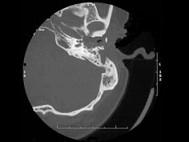

问题 患者,李某,20岁,自幼右耳听力较差,其乳突CT摄片如图所示,可考虑为 ( )

选项 A、先天性胆脂瘤并侵犯耳蜗 B、以上都不是 C、听神经瘤 D、急性中耳炎 E、先天性外耳道狭窄

答案 A